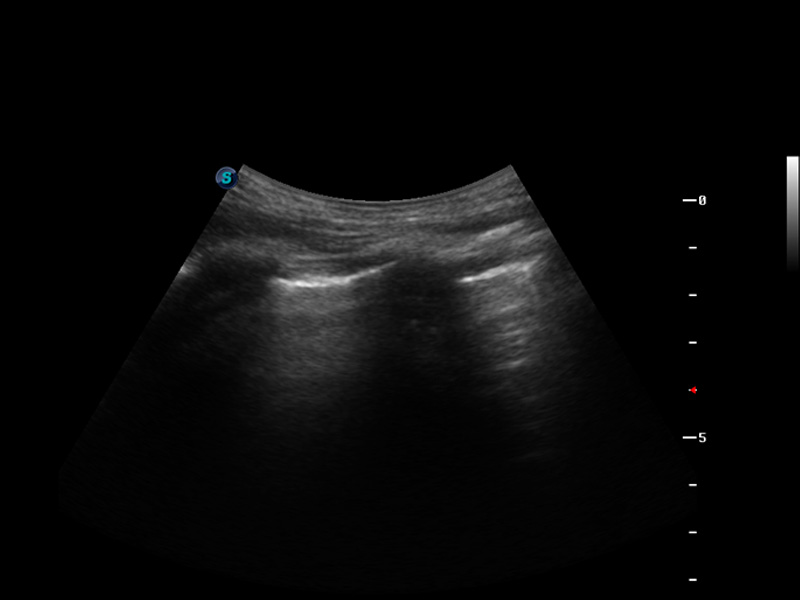

S9便携式彩色多普勒超声诊断仪是玖鼎集团研发的高端便携彩超设备,外观设计新颖、产品性能卓越。S9在便携超声领域采用了突破传统的触摸屏交互设计,并以先进的软件硬件技术和设计理念,为您带来清晰的图像质量、稳定的工作性能和便捷的操作体验。

μ-Scan微米成像